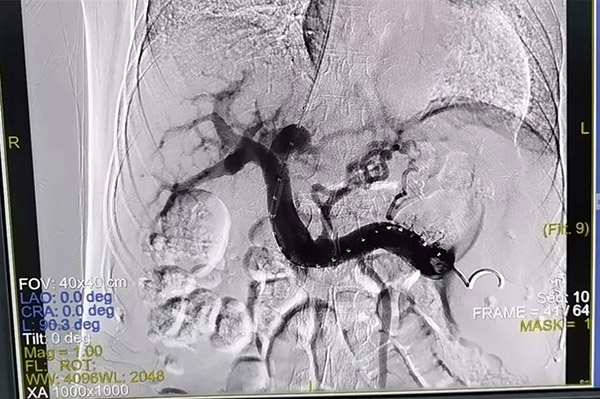

▲患者术前(左)、术后(右)影像对比

术中,经颈静脉穿刺口,马主任将导管、导丝送入患者体内,在影像设备的引导下通过上腔静脉进入到分支肝静脉并放置支架,在门静脉和肝静脉建立创伤程度最小的通路,从而降低门静脉压力。